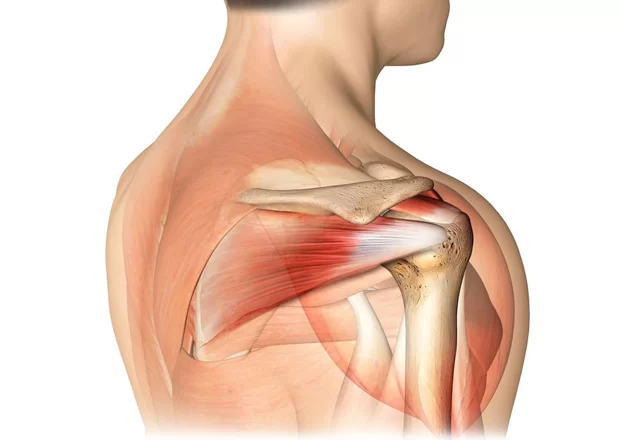

تعتبر أوتار الكتف الدوارة من أهم المكونات التشريحية في جسم الإنسان، فهي تساهم في استقرار مفصل الكتف وتسمح بتحريك الذراع في جميع الاتجاهات، وتشمل هذه الأوتار العضلات الأربعة الأساسية: العضلة فوق الشوكة (Supraspinatus)، العضلة تحت الشوكة (Infraspinatus)، العضلة المدورة الصغيرة (Teres Minor)، والعضلة تحت الكتف (Subscapularis)، وهذه الأوتار تعمل بتناسق تام للحفاظ على قوة ومرونة الكتف، ومع ذلك فهي معرضة للإصابة بعدة مشاكل، ومن أهمها اختناق الأوتار الدوارة وهو ما يمكن أن يؤدي على المدى الطويل إلى تمزق جزئي أو كامل للأوتار، وهذا الأمر يؤثر بشكل مباشر على وظيفة الكتف والحياة اليومية للمصاب؛ وخلال السطور القادمة سنقوم بشرح كافة التفاصيل التي تخص سؤال هل اختناق الاوتار الدوارة يؤدي الي القطع ؟ والتعرف علي أفضل دكتور لعلاج اوتار الكتف.

اختناق الأوتار الدوارة Rotator Cuff Impingement يحدث عندما تضغط العظام المحيطة بالكتف على الأوتار أثناء تحريك الذراع، خصوصًا عند رفع الذراع إلى الأعلى أو تحريكها جانبًا ويعد هذا الاحتكاك سببًا رئيسيًا لالتهاب الأوتار وقد يتفاقم مع التقدم في العمر أو مع الإفراط في استخدام الكتف في الرياضات التي تتطلب حركات متكررة فوق مستوى الرأس، ويصاحب الاختناق عادة شعور بالألم أثناء الحركة، ضعف في الكتف، وأحيانًا الطقطقة أو الاحتكاك، وإذا استمر الاختناق لفترات طويلة، فإنه يؤدي إلى تآكل الألياف وتضعف الأوتار تدريجيًا وهو ما يمهد الطريق لتمزق الأوتار الدوارة.

يعد الاختناق المزمن للأوتار الدوارة من العوامل الرئيسة المؤدية إلى تمزق جزئي أو كامل للأوتار، فالتعرض المستمر للاحتكاك يضعف ألياف الأوتار تدريجيًا، وتظهر الدراسات الطبية أن الأشخاص الذين يعانون من اختناق الأوتار لفترات طويلة دون علاج يواجهون خطر تمزق بنسبة تتراوح بين 30% و50% على المدى الطويل، وغالبًا ما يكون التمزق في أوتار العضلة فوق الشوكة (Supraspinatus) لأنها تقع مباشرة تحت منطقة الضغط، ويبدأ التمزق عادة كتمزق صغير جزئي ثم يتطور تدريجيًا إلى قطع كامل، مما يقلل قدرة الكتف على رفع الذراع وحمل الأوزان، ويصاحبه الألم المستمر وضعف العضلات.